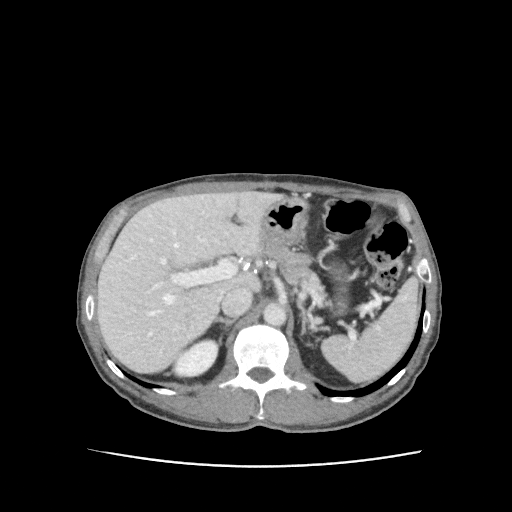

혈액검사상 간수치와 함께 염증수치가 기준치보다 높게 나타났습니다. 간기능에 문제가 있을것으로 사료되었고, 기존 병력을 고려하여 복부CT를 진행하였습니다. 복부CT 촬영상 췌장쪽에서는 병변이 발견되지 않았고, 간의 6번 구획에서 병변이 발견되어 간농양으로 판단되었습니다.

• 복부CT: 간에서 병변이 보이는 소견 복부CT: 간에서 병변이 보이는 소견

• 복부CT: 간 6번 구획 간농양 표시(빨간 동그라미) 복부CT: 간 6번 구획 간농양 표시(빨간 동그라미)